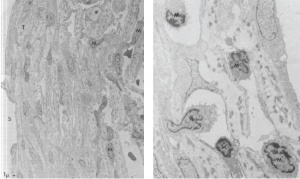

The exact pathophysiology of PSS is still unknown. However, one case of a patient with PSS who underwent trabeculectomy for uncontrolled IOP on medical therapy demonstrated the presence of mononuclear cells in the trabecular meshwork of an intraoperative specimen.[5] On electron microscopy, mononuclear cells were seen intercalated in the trabecular meshwork with long pseudopods, possibly impeding the outflow of aqueous (Figure 1). The origin of these mononuclear cells is still unknown.